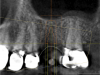

Fig. 19 through Fig. 24 The radiographic guide in place (19); the CBCT scan was taken with the guide seated in the mouth (20); after planning and milling the drill guide was inserted (21), guide in mouth with key and 2-mm bur (handpiece removed for photograph, 22), postoperative x-ray (23), immediate postoperative photograph of healing abutment (24). Surgery was done through tissue punch.